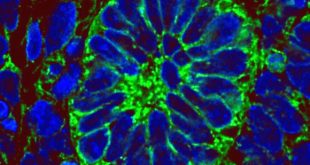

Read More »Researchers Create Functioning Human Kidney Tissue Using Stem Cells

An international research team led by University of Manchester scientists has generated human kidney tissue within a living organism which is able to produce urine. The results appear in the journal Stem Cell Reports. Section from a kidney progenitor-derived mass harvested from a mouse intravenously injected with low-molecular-weight, fluorescein isothiocyanate-labeled …